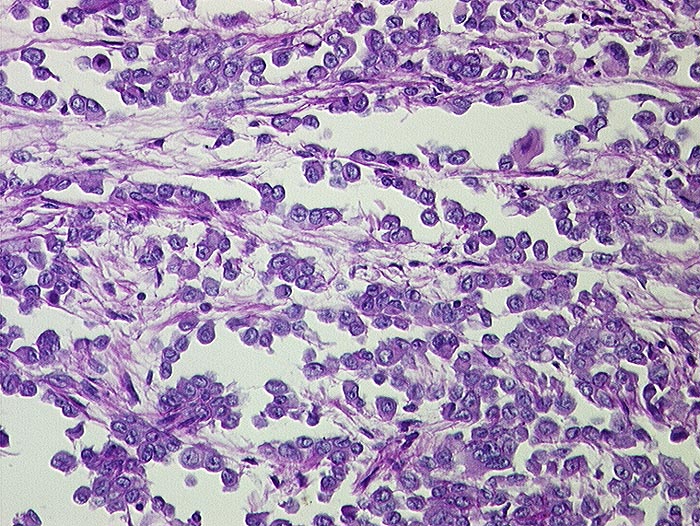

Malignes Mesotheliom epithelialer Typ

Peritoneum

Kubische Zellen kleiden tubuläre Räume aus. Die Tumorzellen haben vesikuläre Kerne mit prominenten Nukleolen.

500ml seröser Ascites. Kleine Metastasen in der Lunge.